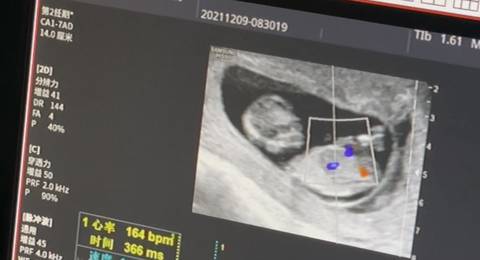

大伙能看看是男宝还是女宝吗 我这是一胎男女都爱哈!

journal_insert_pic_1676707298journal_insert_pic_1676707304journal_insert_pic_1676707317

你好。我们是判断不了男宝宝跟女宝宝的,孕期定期检查,我觉得宝宝健康就好的。祝心想事成 。